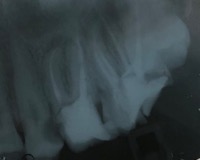

Una corretta terapia canalare con un perfetto sigillo a livello degli apici delle radici è fondamentale. I denti devitalizzati impropriamente possono creare ulteriori problemi che poi andranno a ripercuotersi sulle cure effettuate successivamente come le ricostruzioni e le corone protesiche con conseguente fallimento del piano terapeutico.

Capita spesso di incontrare denti già devitalizzati in maniera impropria che necessitano, seppur asintomatici, di essere ritrattati per evitare che i granulomi infetti visibili radiograficamente si evolvano riassorbendo tutto l’osso sottostante.